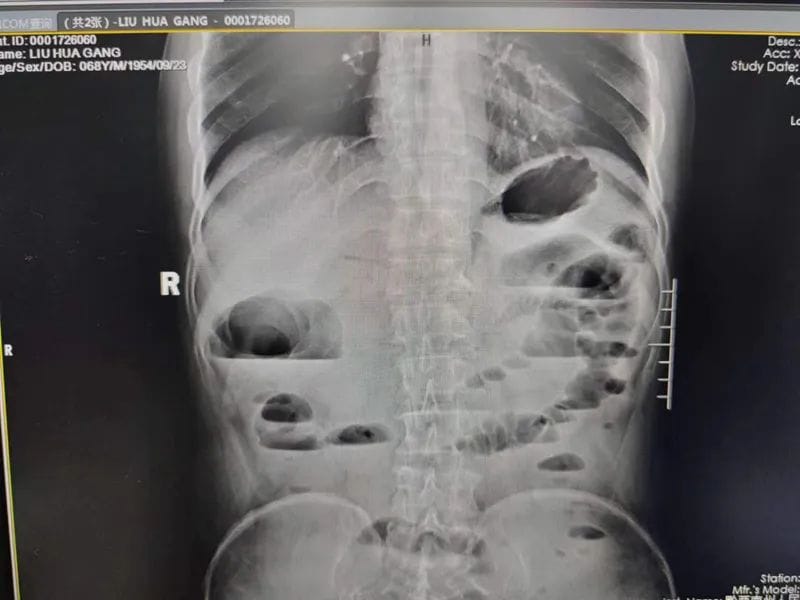

支架置入前

患者,老年男性,腹痛、腹胀、排便困难长达数月之久,近日因病情加重转诊至我院,来时患者呕吐隔夜宿食,腹胀如鼓,入院后,经各项检查初步诊断为横结肠肿瘤并胃、十二指肠及胆胰管、胰头及邻近腹膜组织、周围淋巴结转移,伴近端肠管梗阻扩张。消化内科主任医师郭军博士带领团队对病例进行评估,考虑到患者为恶性肿瘤晚期,全身状态欠佳,而置入肠道支架对患者来说创伤小、并发症少,病人痛苦小,恢复快,无疑是更优的选择。但该病患梗阻部位特殊,即横结肠近肝曲,该部位迂曲且薄弱,且肠道狭窄处仅约0.3-0.4mm大小,支架置入困难,有出血、穿孔、置入失败等风险。医生向患者及家属交代病情及风险后,家属果断选择内镜下结肠支架置入术。该手术是采用金属支架作为肠腔内支撑治疗结直肠恶性梗阻,对于患者来说就像做了一次胃肠镜检查。